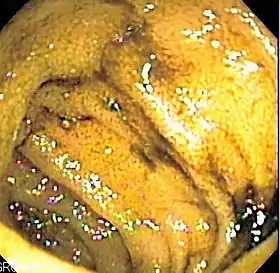

Endoscopic image of normal small bowel | |